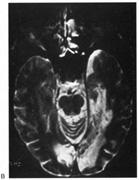

Fig. 10. Striate quadrantanopia. A. A 68-year-old woman with a stroke 3 years previously, causing left inferior quadrantanopia. B. MRI shows infarct of the superior bank of the right calcarine cortex.

The upper and lower banks can also be involved separately. Ischemia can do this because the banks have separate blood supplies. Upper bank infarcts cause homonymous contralateral inferior quadrantanopia (Fig. 10) and lower bank infarcts cause superior quadrantanopia. Although altitudinal defects have been reported occasionally,47,48 most quadrantic defects do not align at the horizontal meridian, because the upper field merges without interruption into the lower field in the depths of the calcarine fissure. Thus it has been argued that quadrantic defects that respect the horizontal meridian are caused by involvement of area V2, surrounding striate cortex,49 which remains controversial. Quadrantanopias are three times more common with striate lesions than with optic radiation lesions.33 Striate quadrantanopias are more frequently isolated signs but can be associated with other signs of higher cortical visual dysfunction, such as pure alexia or hemiachromatopsia, whereas optic radiation quadrantanopias usually are accompanied by hemiparesis, dysphasia, or amnestic problems.33